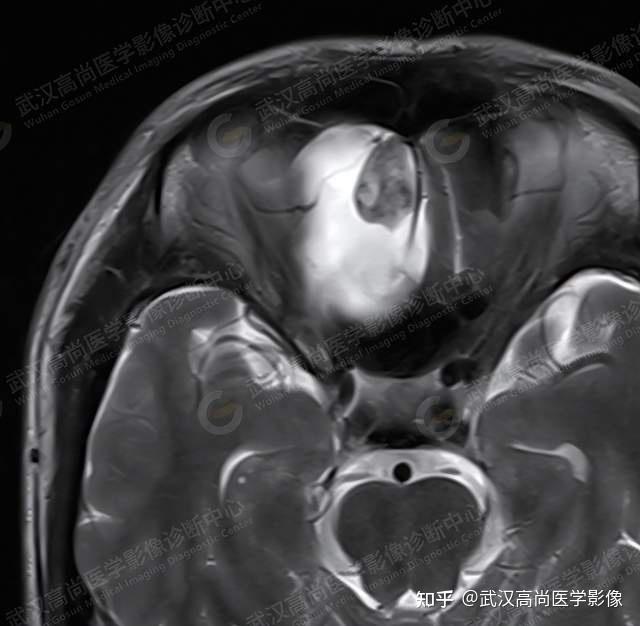

罕见的前颅窝神经鞘瘤武汉高尚医学影像

图片尺寸640x626